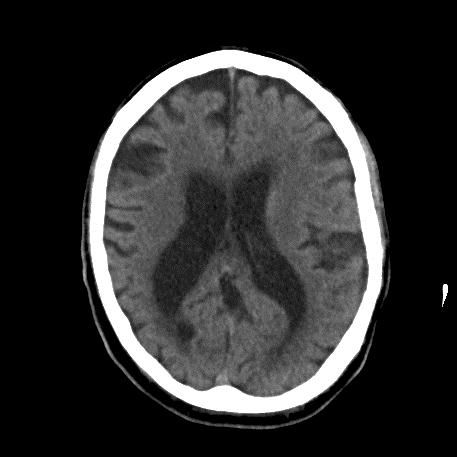

The picture shows a brain scan of someone with a combination of Alzheimer’s type dementia and a vascular dementia. The amount of brain (which is grey) is reduced. The black shadows in the middle are the ventricles which are enlarged and the black lines around the outside show the increased gap between the folds of the brain. This person has a moderate dementia. In severe dementia changes are often more marked.